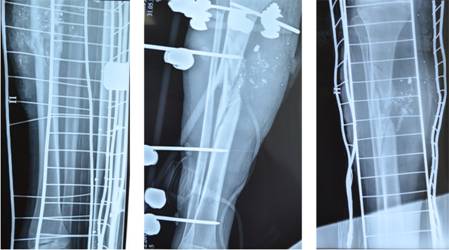

Рис. 3. Созревание регенерата в нижней трети большеберцовой кости, в верхней трети – консолидация отломков (а). Вид ноги в аппарате в процессе фиксации (б)

Через 28 дней проведен второй этап билокального остеосинтеза. Демонтирована подсистема на стопе. Одновременно с хирургической обработкой правой голени проведен перемонтаж аппарата Г.А. Илизарова. В процессе обработки раны удалены участки сухого некроза. Для закрытия места стыка отломков при открытом их сопоставлении проведена ротационная комбинированная пластика правой голени, чтобы обеспечить возможность полноценной консолидации. Использован несвободный ротационный лоскут размерами 4 ´ 6 см с дистальным основанием, само же ложе образовавшегося дефекта кожи замещено свободным лоскутом по Парину, взятым по внутренней поверхности этого же бедра. При ревизии раны выявлено, что раневой канал уходил на задневнутреннюю поверхность голени в толщу медиальной головки икроножной мышцы с образованием большой полости, распространяющейся дистально. Некротизированные и лизированные ткани удалены. Сопоставленные отломки большеберцовой кости фиксированы спицами, проведенными в поперечном направлении и закрепленными в кольцах аппарата Илизарова в режиме легкой компрессии. Процесс консолидации отломков в месте огнестрельного дефекта кости совпал по времени со сроками созревания костного регенерата в нижней трети большеберцовой кости (рис. 3).

Общий срок фиксации в аппарате составил 8 месяцев. Достигнуты полная консолидация отломков большеберцовой кости и хорошая функция нижней конечности. Восстановлена тыльная флексия стопы, амплитуда движений в голеностопном и коленном суставах сохранена (рис. 4).

Рис. 4. Результаты лечения. Консолидация и формирование полноценной костной ткани на месте формирования костного регенерата, функция смежных суставов сохранена